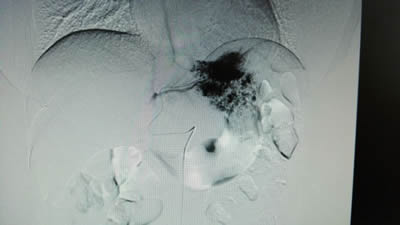

术前:DSA下右肝7×5cm的肝血管瘤成像 术前:DSA下左肝5×4cm的肝血管瘤成像

术中:DSA下肝左右叶血管瘤栓塞治疗后成像(见图标1、2) 半年后返院复查,肝左右叶血管瘤基本消失(见图标1、2)